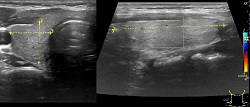

USG Tarczycy.